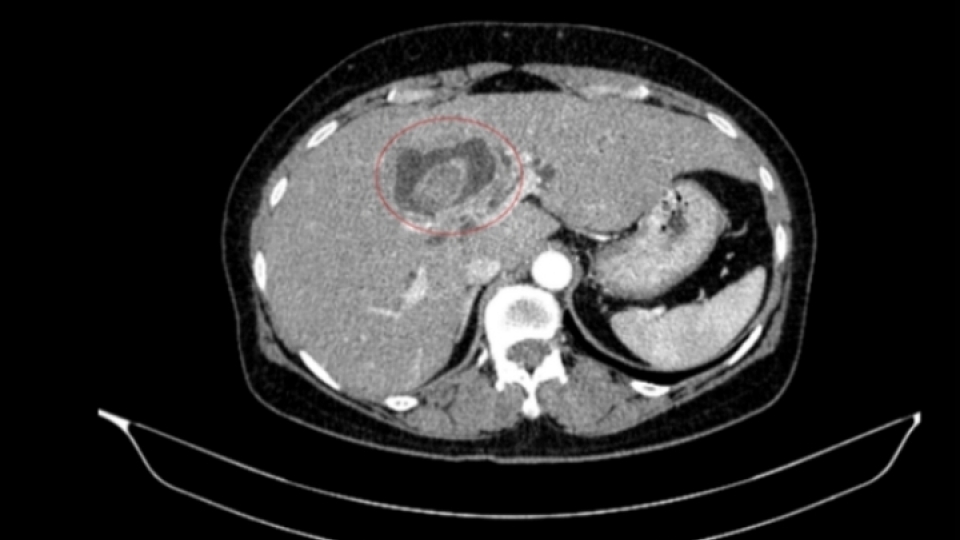

Thông tin từ Bệnh viện Bạch Mai, nam bệnh nhân nhập viện trong tình trạng tiểu khó kéo dài. Qua thăm khám và thực hiện các kỹ thuật cận lâm sàng như chụp cắt lớp vi tính, cộng hưởng từ, xạ hình xương và đặc biệt là PET/CT, các bác sĩ phát hiện tổn thương tại tuyến tiền liệt cùng nhiều khối u ở phổi, tuyến thượng thận và xương.

Thách thức lớn nhất trong trường hợp này là xác định bản chất các tổn thương: đâu là khối u nguyên phát, đâu là di căn. Nếu chẩn đoán không chính xác, việc lựa chọn phương pháp điều trị có thể sai lệch, ảnh hưởng trực tiếp đến hiệu quả điều trị.

Kết quả sinh thiết và phân tích mô bệnh học kết hợp hóa mô miễn dịch giúp làm rõ: khối u phổi là ung thư biểu mô tuyến của phổi, trong khi khối u tuyến tiền liệt là ung thư biểu mô tuyến với điểm Gleason 9 - thuộc nhóm nguy cơ cao. Hai loại ung thư này có nguồn gốc hoàn toàn khác nhau, không phải di căn chéo.